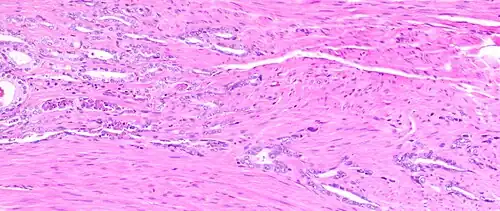

The connective tissue of the prostate is made up of fibrous tissue and smooth muscle.[2] The fibrous tissue separates the gland into lobules.[2] It also sits between the glands and is composed of randomly orientated smooth-muscle bundles that are continuous with the bladder.[11]

Histology of normal prostate, H&E stain, with benign features: Glands are rounded to irregularly branching, with an inner layer of epithelial cells surrounded by an outer layer of basal cells. They are surrounded by ample stroma. -

Histology of prostate with gradually increasing simple atrophy from left to right, H&E stain. Crowding and angulation may mimic that of adenocarcinoma, but there is nuclear basophilia rather than atypia, and occasional basal cells can still be seen.